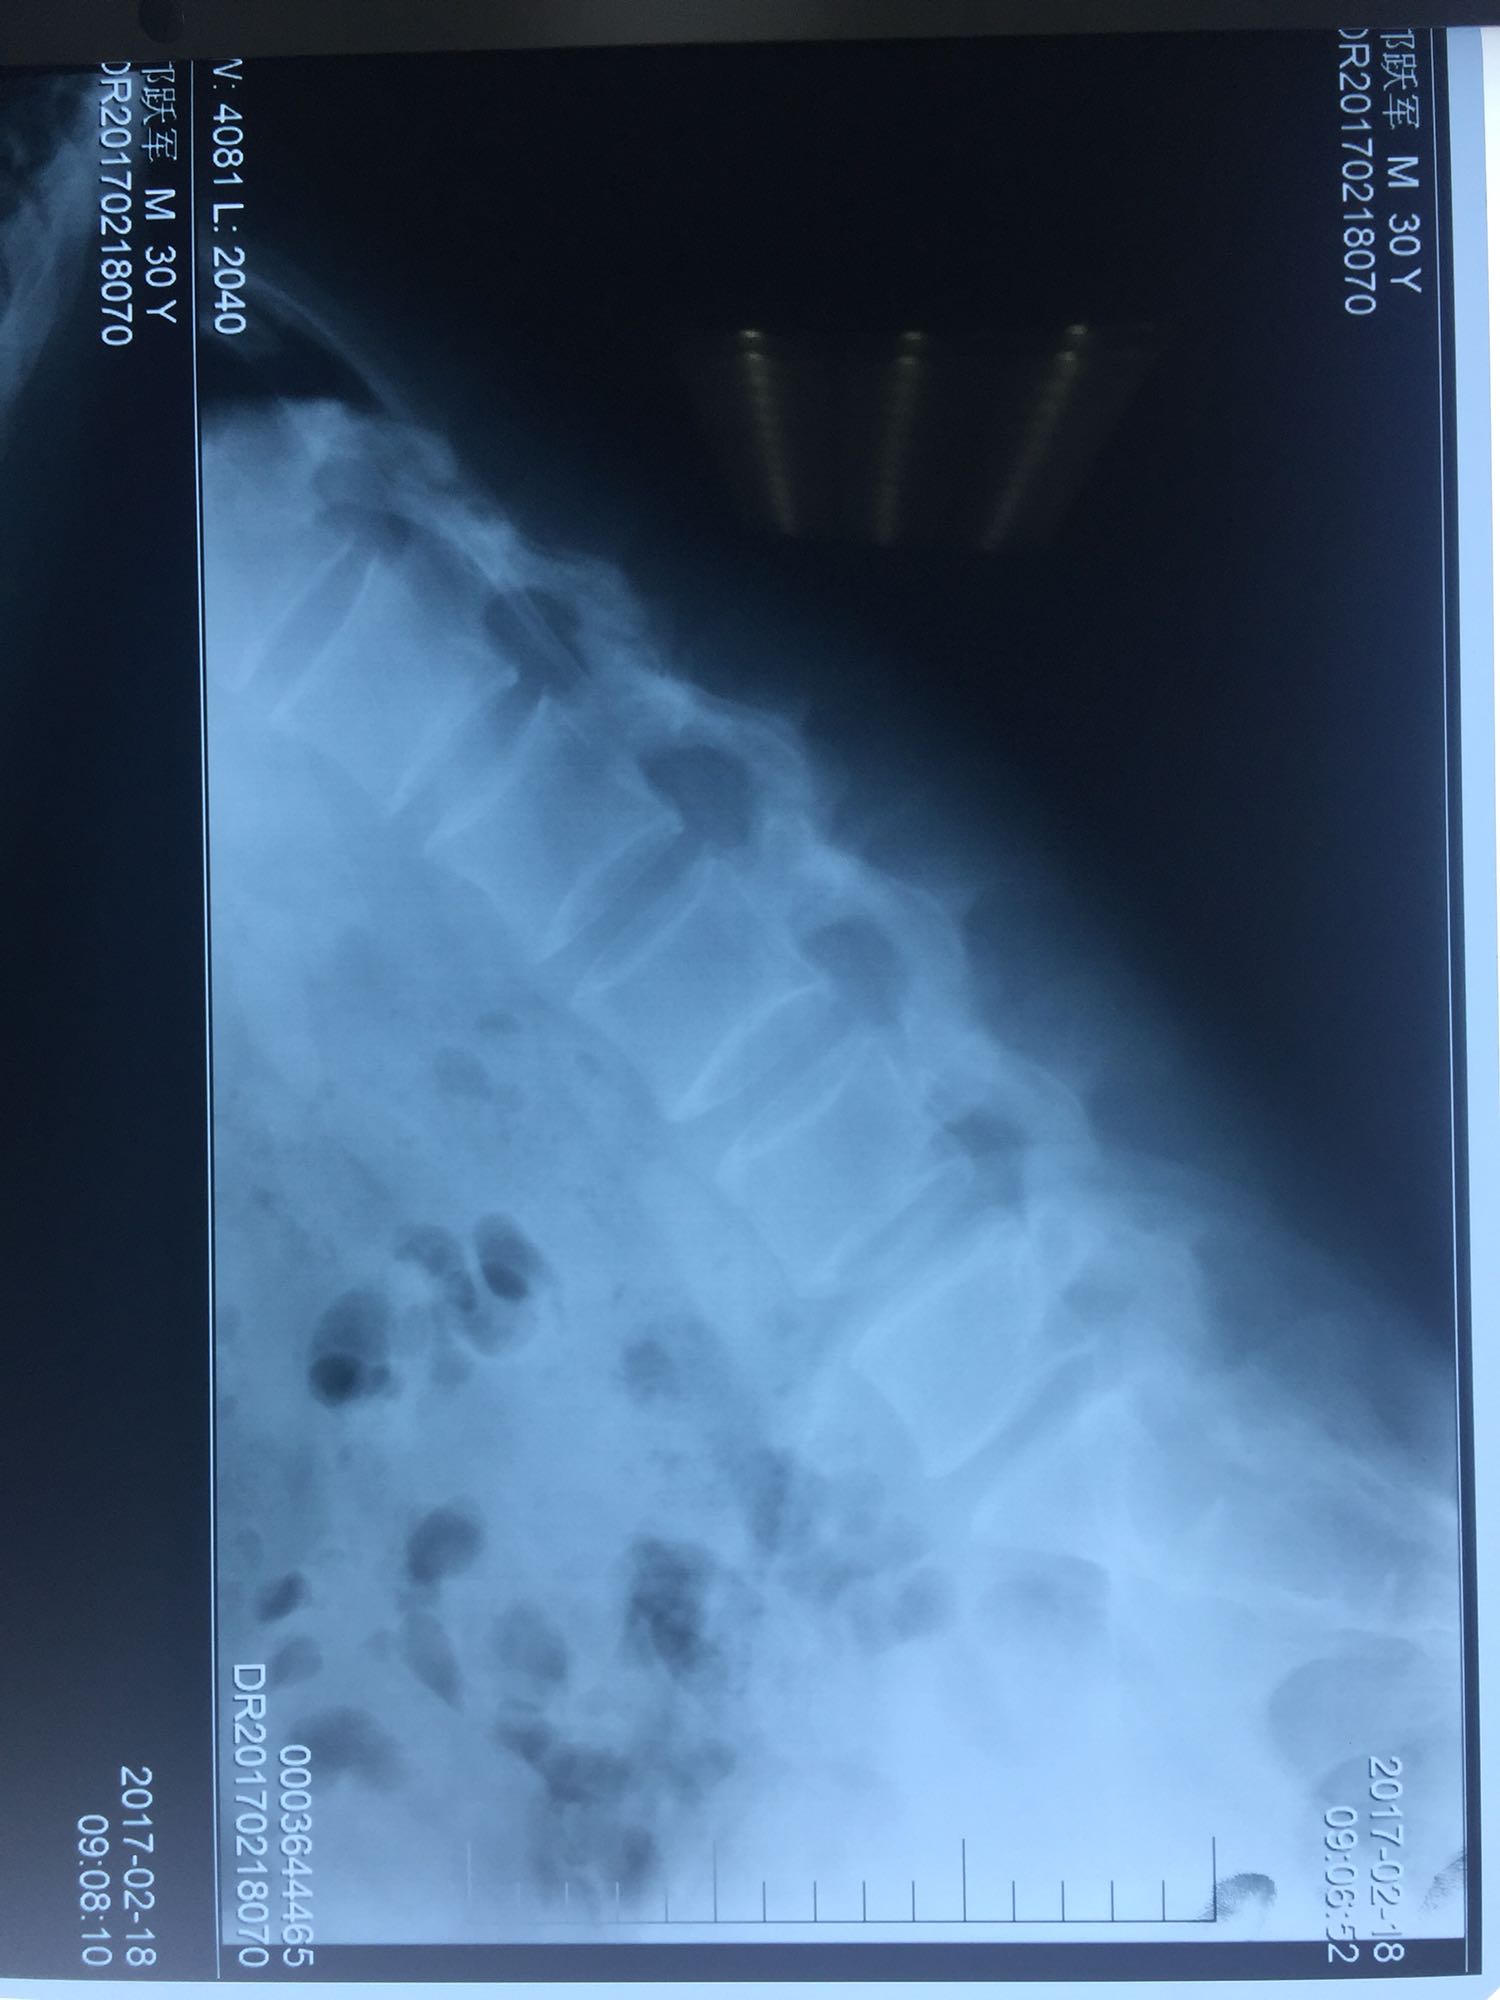

腰骶部肌紧张,腰5骶1棘间及左侧椎旁有压痛及放散痛,左侧坐骨神经出孔处有压痛及放散痛,左侧足背外侧及足底部皮肤感觉麻木,左侧直腿抬高试验阳性(30度)。

诊断:腰5骶1椎间盘突出症 治疗方案:椎间孔镜下经椎板间入路髓核摘除术